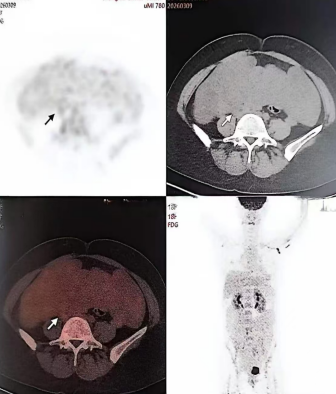

患者既往有子宫肌瘤手术史,因阴道不规则流血20天在外院就诊,MRI提示盆腹腔多发肿块,一度怀疑为卵巢恶性肿瘤,患者与家属承受着巨大的心理压力。2026年3月6日,患者于上海某医院复查MR,结果进一步明确:下腹部及盆腔多发结节肿块,部分与子宫肌层分界不清,子宫肌层及右侧前盆壁肌层亦见多发结节,高度提示静脉内平滑肌瘤病,并存在肌瘤播散可能。患者的 PET / CT 检查示:腹、盆腔多发囊实性肿块,FDG 代谢略高,卵巢来源MT 可能,两侧髂血管旁淋巴结 M 待排,腹膜、左上肺肿块(3.0cm) M 可能;双侧颈部、左侧腋窝淋巴结炎性增生可能,肝脏钙化灶,胆囊结石。